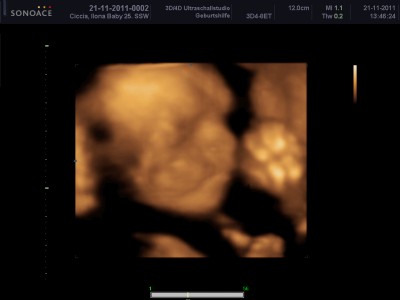

wieder zuhause =) mit 200 fotos und einer 1-stündigen dvd :räusper:

Weil sich die kleine immer nur mit hand vor dem gesicht gezeigt hat, mussten wir über ne stunde schallen bis sie sich mal bequemt hat sich zu zeigen *g*

Ich hänge euch mal ein Bild mit an.

ERINNERUNG21112011_0155.JPG

ERINNERUNG21112011_0180.JPG

ilo: sind das schöne Bilder, so 3 D find ich eh viel besser als die normalen. Rosa ist auch nicht so meins, deswegen hab ich da nie viel von gekauft. Aber pass mal auf, wenn Madame dann selber aussuchen will was sie anzieht. Pferde müssen drauf sein oder Prinzessinen, was soll man machen? :?: